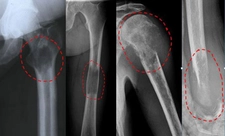

• Görüntüleme testleri (BT, MR, PET taramaları)